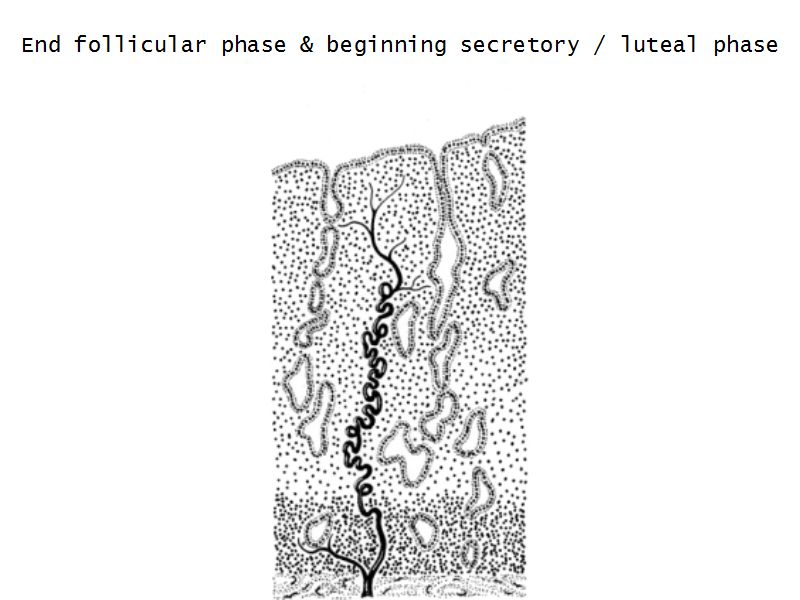

Menstrual cycle

- Luteal phase

Luteal phase

- Thickening endometrium

- Edema

- Endometrial gland secretion

- Glands

- Glandular cells at apex

- Basal accumulation glycogen

- Helical arteries reach superficial regions